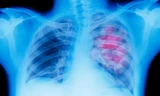

Bệnh nhân được thăm khám toàn diện và phát hiện phổi có nhiều bóng giãn, phế nang nhiều bóng khí do phổi bị thủng, tràn khí vào màng phổi khiến phổi bị xẹp, không giãn nở gây khó thở.

Bác sĩ chuyên khoa 2 Khiếu Mạnh Cường, khoa Ngoại Gan mật và Ung bướu (Bệnh viện Bệnh Nhiệt đới Trung ương), cho biết: “Tràn máu - tràn khí màng phổi, tràn khí màng phổi có van là tình trạng khá nguy hiểm.

Nếu không được xử lí đúng cách và kịp thời thì tình trạng này sẽ ngày càng nghiêm trọng. Bệnh nhân sẽ bị suy hô hấp hoặc mất máu có thể gây sốc trong trường hợp tràn máu, tràn khí và nguy cơ tử vong cao”.